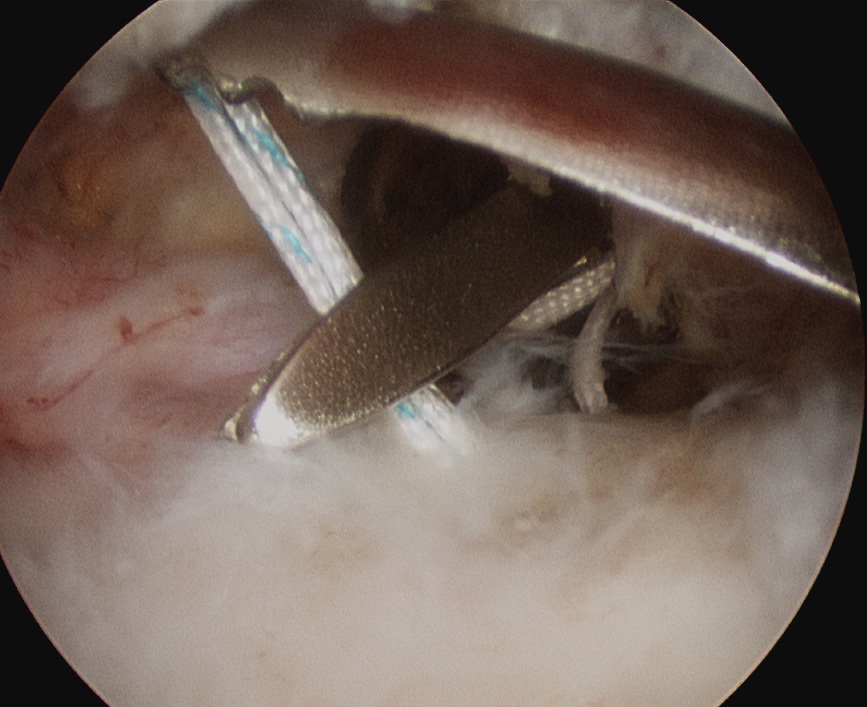

Double row

- either pass second lateral row of anchors or

- use foot print anchors, retrieve previous sutures

- can make suture bridge configuration

- check repair via lateral portal